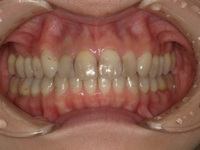

これからも「ちりゅう歯科にいけば大丈夫!」と信頼し続けていただけるよう、困ったことがあれば、どんなことでも対応します。当院の治療のゴールは「不自由なく噛めて、見た目にもコンプレックスがない状態」。その目標に向かって、一回一回が真剣勝負の思いで診療に携わり、地域にお住まいの方々のお口の健康をサポートいたします。

私はこれまでの歯科医師人生で、虫歯や歯周病、歯の根にある神経の処置である根管治療、入れ歯、インプラント、美容診療など、幅広く取り組んでまいりました。例えば虫歯治療では、痛みのある歯だけでなく、噛み合わせなどお口の中を総合的に考えたアドバイスや立案をし、歯を長持ちさせる処置を提供することを心がけています。